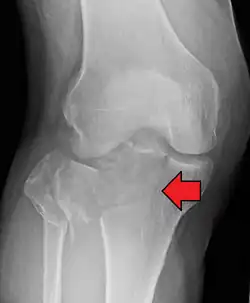

Subtle tibial plateau fracture on an AP X ray of the knee -

A tibial plateau fracture seen on X-ray

In all injuries to the tibial plateau radiographs (commonly called x-rays) are imperative. Computed tomography scans are not always necessary but are sometimes critical for evaluating degree of fracture and determining a treatment plan that would not be possible with plain radiographs.[10] Magnetic Resonance images are the diagnostic modality of choice when meniscal, ligamentous and soft tissue injuries are suspected.[11][12] CT angiography should be considered if there is alteration of the distal pulses or concern about arterial injury.